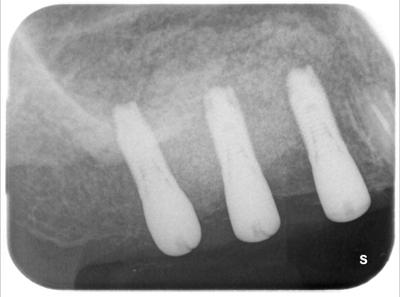

術前

インプラントを埋入するにあたり、十分な骨量がないため、自家骨+バイオス+リグロス使用。

インプラント埋入直後

43┛根管治療、8┛抜歯

十分骨が移植され、インプラントが埋入された。